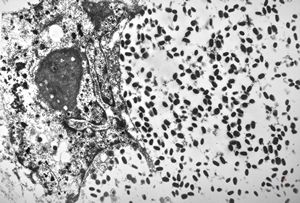

M, 28y. | leishmaniosis … skin of the cheek

M, 28y. | leishmaniosis … skin of the cheek